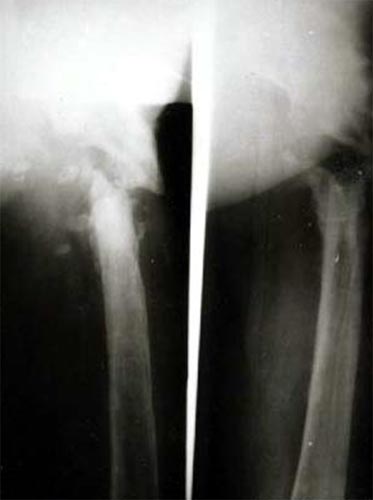

患者股骨粗隆下骨折、骨不连,左图为手术前,显示假关节形成,右图为手术内固定后,关节功能恢复